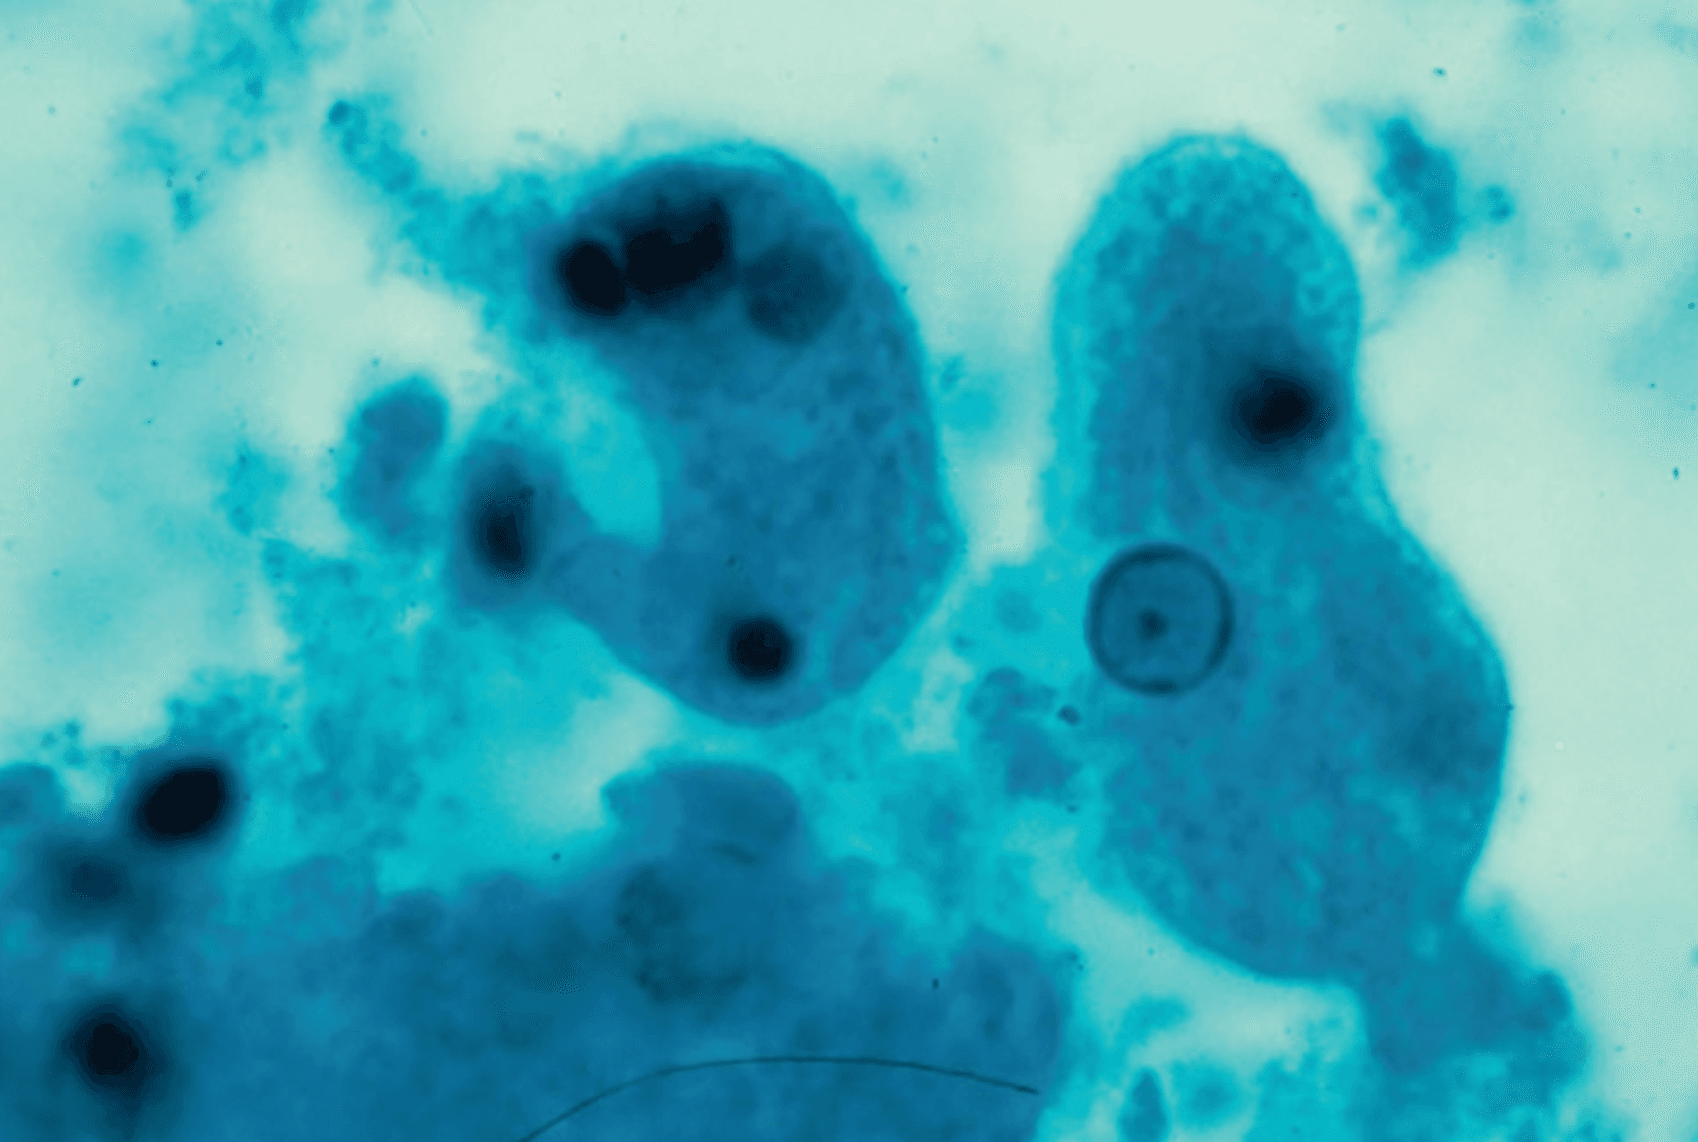

Laboratory studies: WBC 15.4 k/mcL with 88% neutrophils, hemoglobin 11.8 g/dL, platelets 388 k/mcL. Alkaline phosphatase 224 U/L, total bilirubin 1.6 mg/dL, AST 58 U/L, ALT 64 U/L, albumin 2.9 g/dL. Creatinine 0.9 mg/dL. Blood cultures are drawn and remain negative at 48 hours. CT of the abdomen with contrast reveals a single 9 cm hypodense, rim-enhancing lesion in the right lobe of the liver. A diagnostic aspirate is performed and the fluid is described as chocolate-brown and odorless, with no organisms on Gram stain and negative bacterial culture. The image below was obtained from the lesion aspirate.

Microscopy of the hepatic aspirate: a large trophozoite with ingested erythrocytes visible within the cytoplasm.